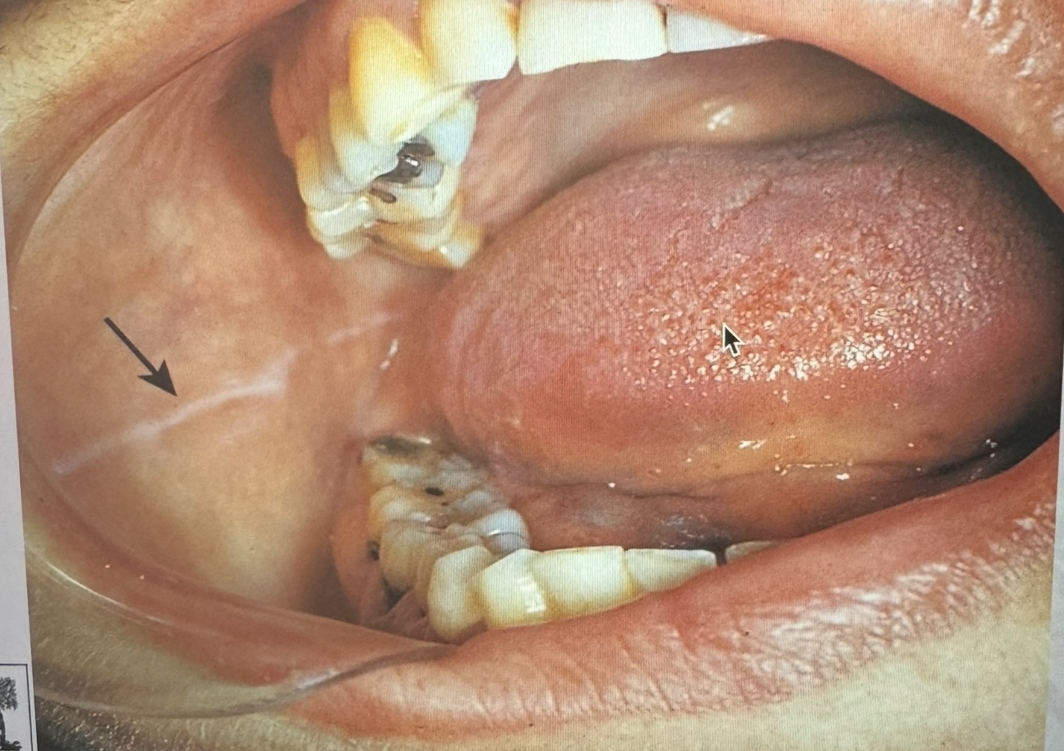

<p>Identify </p>

Linea alba